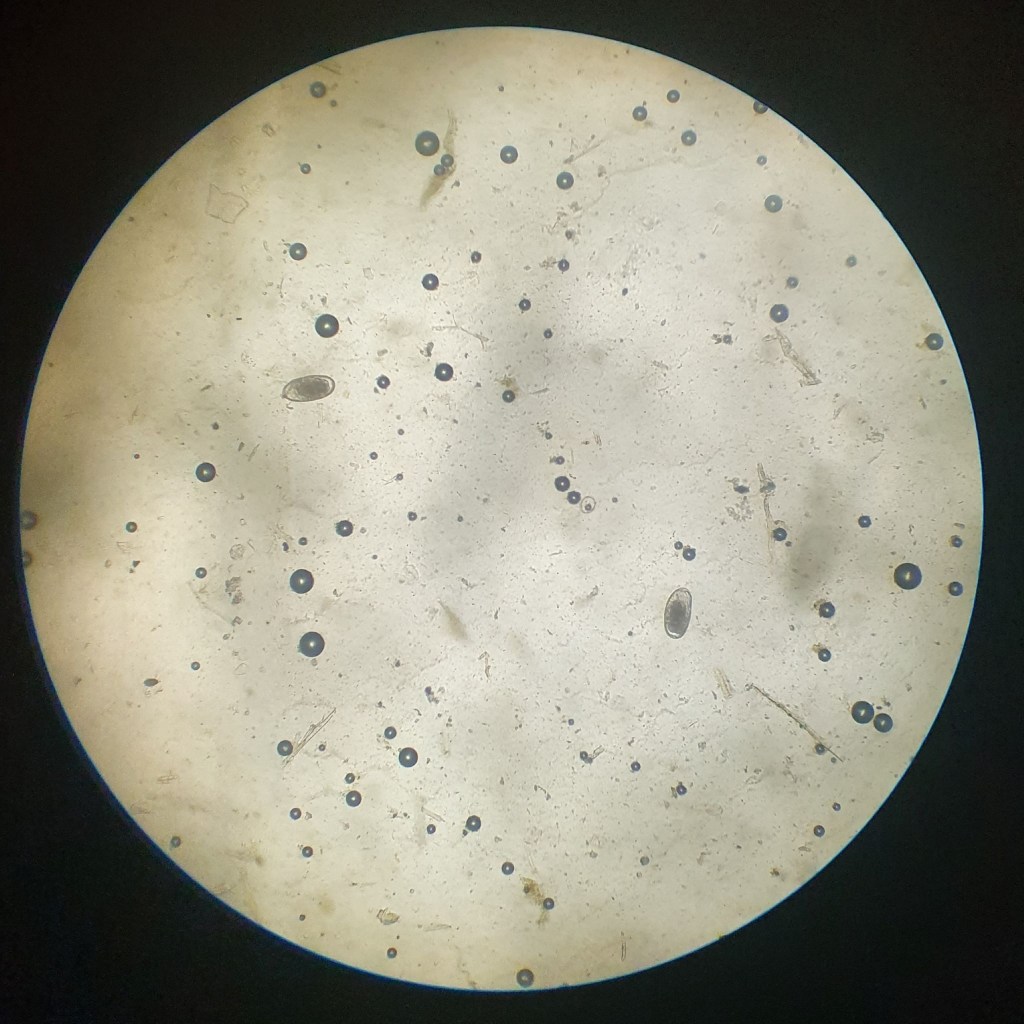

Mestonderzoek

Via mestonderzoek worden voornamelijk bloedworminfecties opgespoord. Hoeveel keer per jaar je dit laat uitvoeren hangt af van het managment rondom je paarden (stalling, weidegang, uitmesten,…) en de infectiegraad tijdens voorgaande onderzoeken. Geen standaard-riedeltjes hier maar echt een op maat gemaakt schema ;).